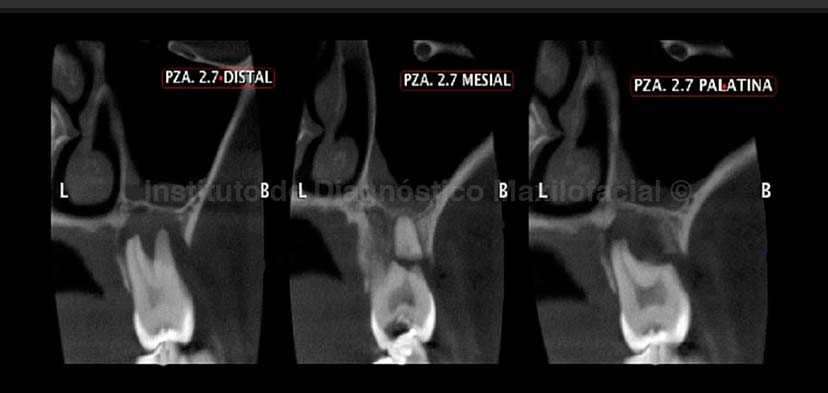

La tomografía computarizada de haz cónico (cone beam), en cortes transaxiales, tangenciales y reconstrucción 3D; nos muestra un trazo de fractura a nivel del tercio cervical de la raíz mesial de la pieza 27 (Fig 2 ,3 y 4).Así mismo observamos un proceso osteolítico perirradicular extenso que condiciona la reabsorción de las raíces distovestibular y palatina, además del engrosamiento de la mucosa sinusal, la reconstruccion 3D confirma todos estos hallazgos.(Fig.2 ,3 y 4).